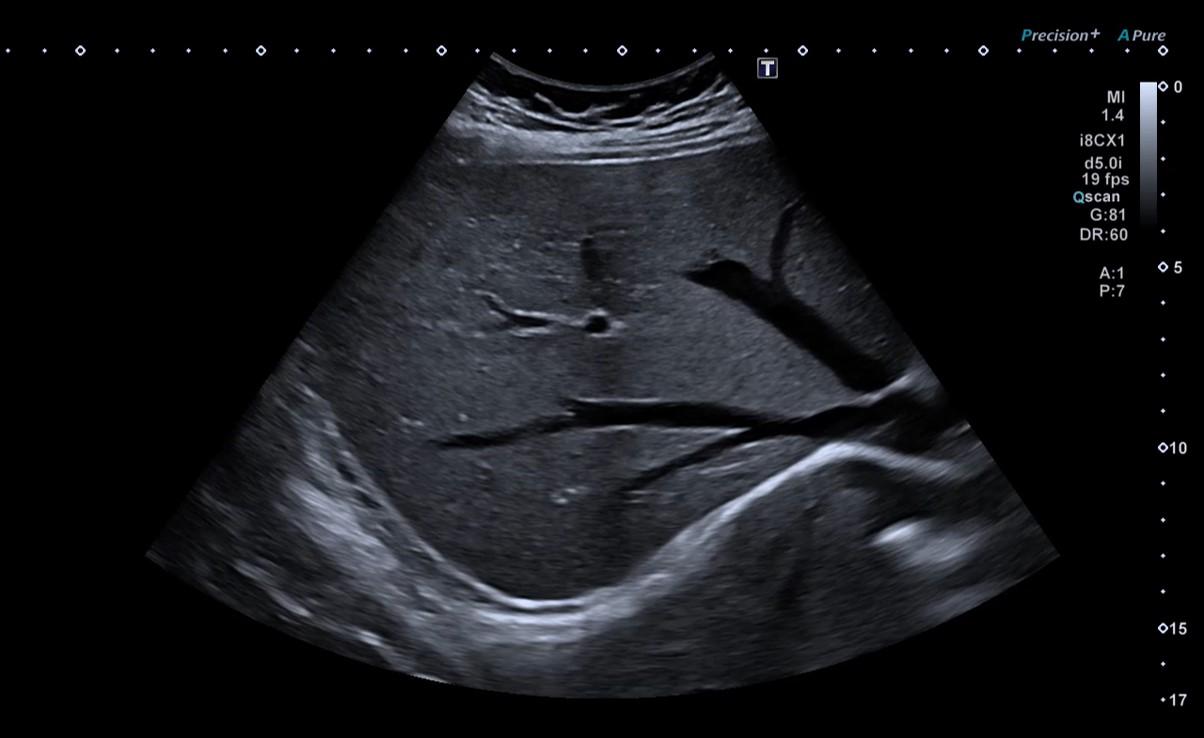

A Ecografia utiliza ultra-sons de alta frequência emitidos por uma sonda e transmitidos através dos tecidos que os refletem para formar uma imagem da região examinada.

As imagens em movimento são observadas em tempo real num ecrã e interpretadas por um médico especializado em imagiologia.

De forma geral, a ecografia é um exame muito versátil que permite detetar alterações estruturais e funcionais em diferentes órgãos e tecidos. É possível identificar massas, quistos e nódulos, bem como sinais de inflamação ou infeção. Através do Ecodoppler, pode ainda avaliar o fluxo sanguíneo, sendo útil no estudo de doenças vasculares. Este exame possibilita também a deteção de cálculos e obstruções em órgãos como os rins ou a vesícula, assim como alterações na morfologia de diversos órgãos internos. Dependendo da área avaliada, a ecografia permite determinar a presença, localização, extensão e características das lesões, além de ser uma ferramenta fundamental para o acompanhamento da evolução das patologias ao longo do tempo.

- Ecografia abdominal: avaliação do fígado, vesícula, pâncreas, baço e outros órgãos abdominais.